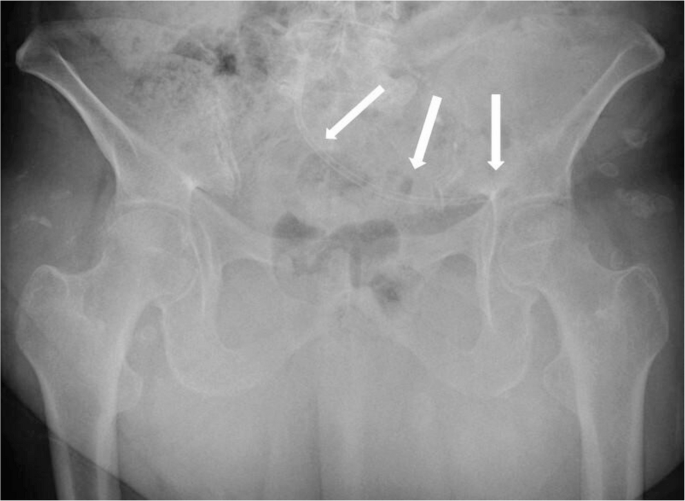

影像学检查显示,一根弯曲的胆道支架从盆腔中部延伸至左下腹,经过髂耻线和髂坐线。即使在单投影X光片上,也能清晰看到支架的远端外侧末端,其末端终止于左髋臼顶部。支架周围局部骨溶解变化表明支架与骨骼有直接接触。X光片未显示髋关节周围有渗出、皮质边界模糊或硬化现象(图1)。增强腹部和盆腔CT显示支架正确放置在胆总管内,而另一根支架则移位至乙状结肠。移位的支架部分位于结肠腔内,其余部分穿透了结肠壁,穿过脂肪层、左髂腰肌筋膜和髂肌,越过髂骨的弓状线,导致髋臼前部出现局部骨质侵蚀,边缘清晰,轮廓平滑(图2)。在支架附近的小范围内观察到单层线性骨膜反应(图2)。在更外围的区域,髂骨上观察到向髋臼前部延伸的硬化改变,以及皮质不规则和小的硬化边缘的侵蚀灶(图3)。

图1

这是一张前后位髋部X光片。可见一根弯曲的胆道支架从盆腔中部延伸至左下腹,经过髂耻线和髂坐线,支架的远端外侧末端终止于左髋臼顶部(箭头所示)